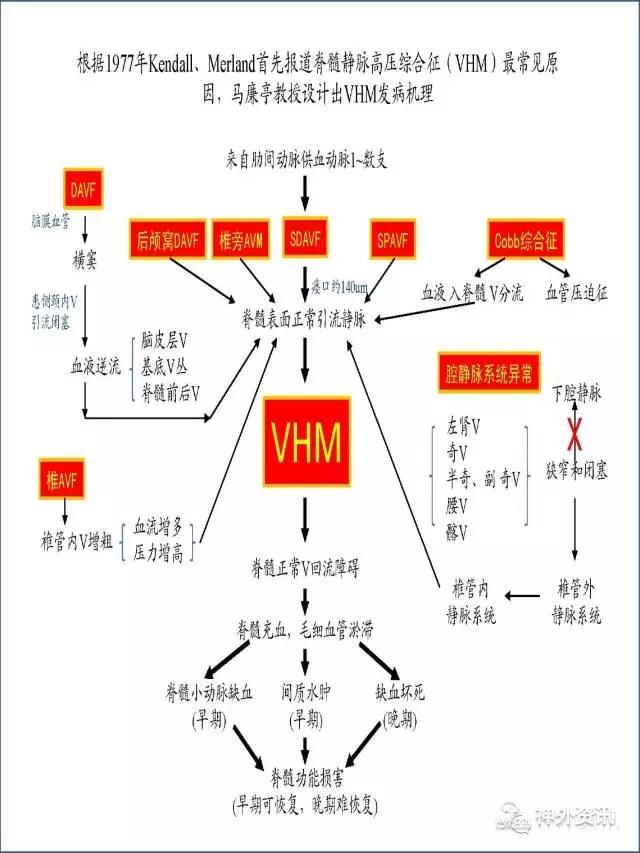

图12: VHM导致脊髓损伤的机制示意图。VHM:脊髓静脉高压综合征;AVF:动静脉瘘DAVF:硬脑膜动静脉瘘;SDAVF:硬脊膜动静脉瘘;SPAVF:软脊膜动静脉瘘:AVM:动静脉畸形;V:静脉。